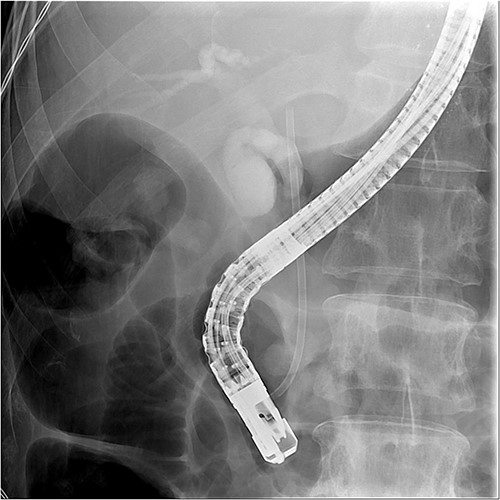

ERCP with a sphincterotomy was performed. After several attempts of wire-guided cannulation, successful CBD cannulation was achieved and confirmed by the cholangiography. Due to distal CBD stricture, we then used endoscopic balloon dilation repetitive of trying, we assumed deep cannulation to pass through the CBD stone was achieved because the guide wire advanced smoothly (Fig. 2).

Successful wireguide CBD cannulation to pass through the opacified CBD stone following by cholangiography.